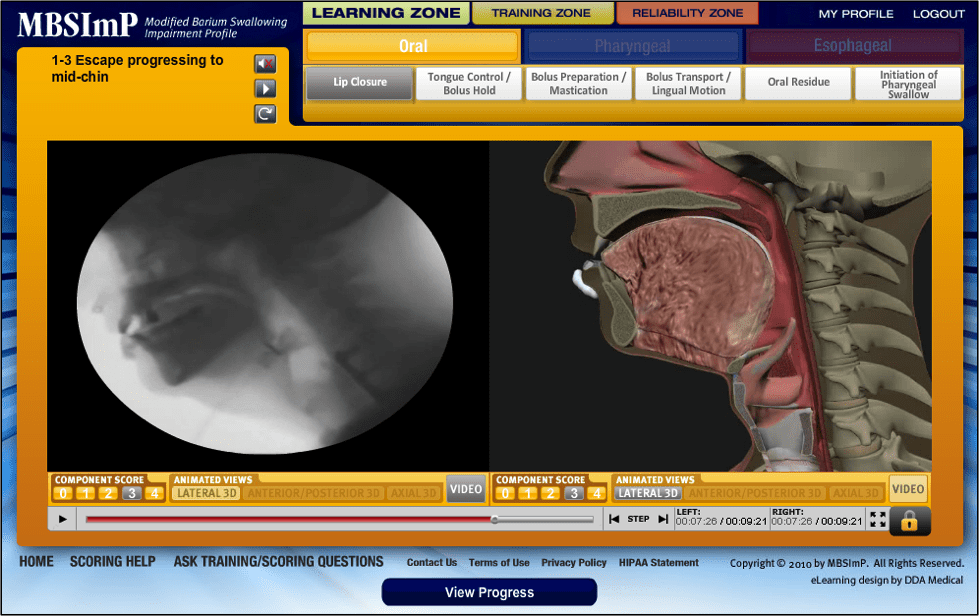

MBSImP Oral Dysphagia